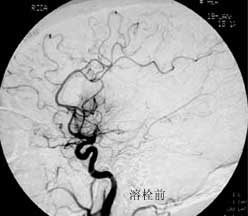

三、闭塞性脑血管病

----闭塞性脑血管病,如急性脑梗塞引起的偏瘫、颈动脉或椎基底动脉狭窄所致短暂性脑缺血发作(TIA)及可逆性神经功能障碍(RIND),视网膜中央动脉或中央静脉闭塞引起的视力减退,静脉窦血栓性形成引起的颅内压增高等,均可通过血管内的介入治疗得以改善,介入治疗的方法分溶栓、血管成形术或支架置入,根据病变选择不同的治疗方法。

2.急性梗塞动脉内接触性溶栓治疗的适应症:

(1)发病6小时内;

(2)CT或MEI检查没有梗塞及出血表现;

(3)对大脑中动脉卒中者,133XESPECT检查显示CBF残存超过每分钟15ml/100g;

(4)血管造影证实颅内血栓及部位;

(5)基底动脉溶栓可延至发病后48小时。